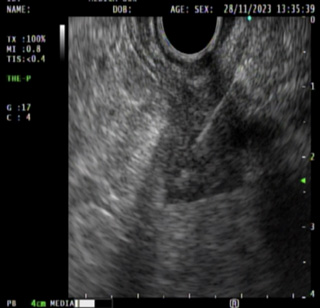

use 02

Imagen 2.Tumor gástrico dependiente de la capa muscular.